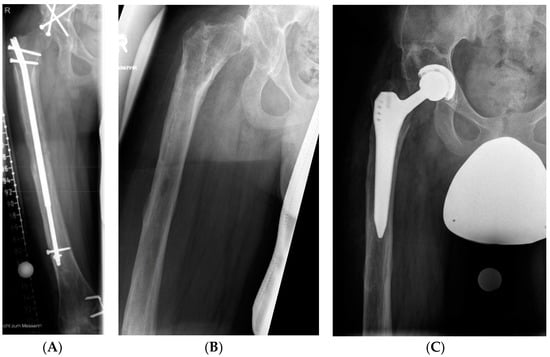

| Major complications (n = 6 in 5 patients) | 2 | Premature consolidation | Reosteotomy | None |

| 2 | Fracture of the femur | Exchange nailing | None | |

| 1 | Deep infection | Retrieval of the lengthening nail, external fixation | Pain, restricted range of movement | |

| 1 | Hip subluxation | Total hip arthroplasty | ||